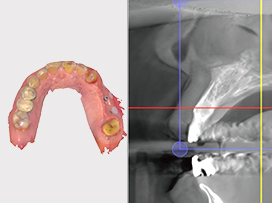

• CT를 이용한 3D 진단

CT 촬영한 3차원 데이터와 구강 모형을 통해 뼈, 잇몸, 신경을 통합적으로 고려하여 정밀 진단합니다.

• 컴퓨터로 수술 계획 수립

컴퓨터로 모의 수술을 통해 수술 위치를 설정하고, 그대로 수술될 수 있도록 맞춤형 가이드를 제작합니다.